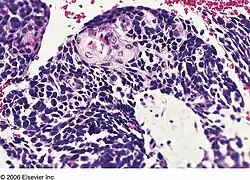

| Combined small cell lung carcinoma containing a component of squamous cell carcinoma | |